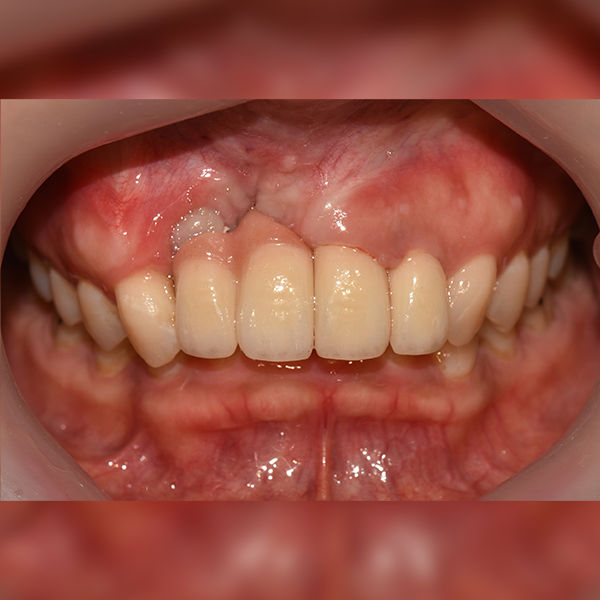

3. 症例.111 30代 趙*善 2018-11-30 / 2019-12-10

上顎 / 前歯部 / 3本以下 / 骨移植

症例.111 30代 趙*善 2018-11-30 / 2019-12-10

After After

Before Before